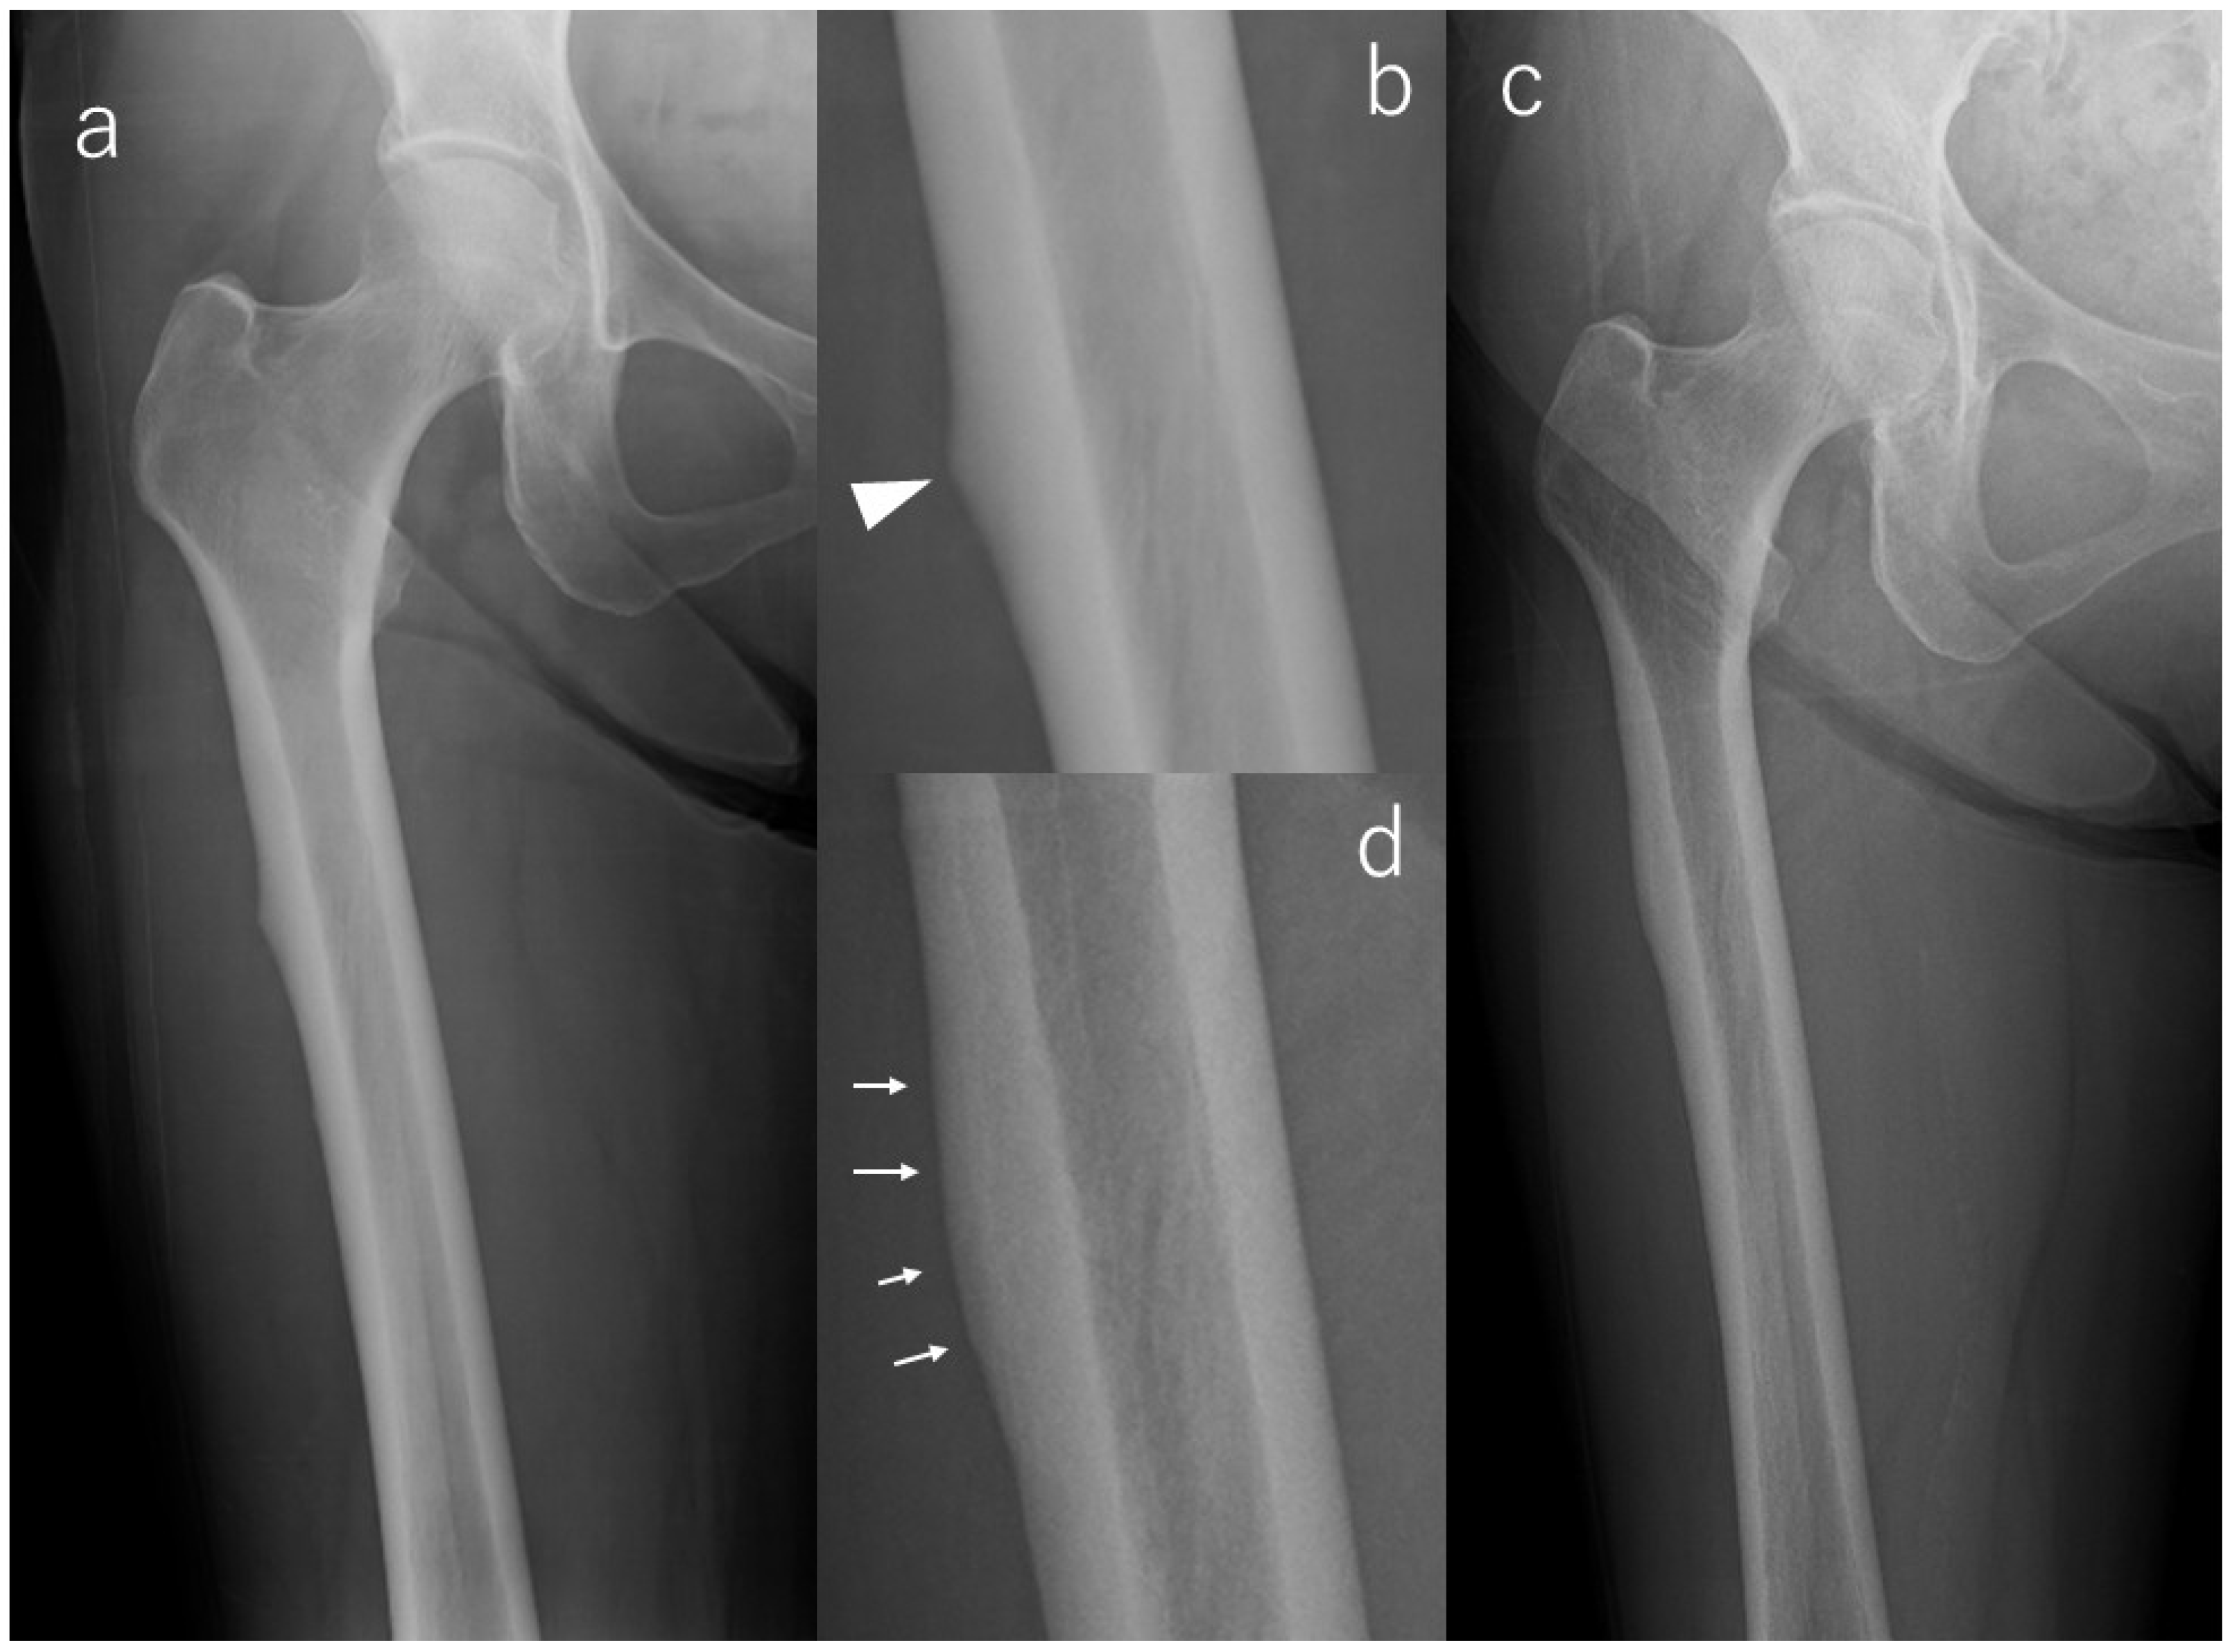

In contrast, a majority of limbs demonstrated favorable radiographic evolution. Lesion reduction was observed in six limbs, with three showing notable flattening of cortical beaking and three demonstrating decreased periosteal flaring. All of these improvements occurred without symptom onset, emphasizing that radiographic remodeling may proceed independently of clinical manifestations. Case #3 serves as a representative example (Figure 2): initial postoperative imaging demonstrated a lateral subtrochanteric cortical prominence without a fracture line, which progressively flattened over 112 months of surveillance. This improvement was already visible at 36 months and remained stable thereafter, with no radiolucent line ever appearing.

Figure 2. X-rays of Case #3. (a): Radiograph at the time of injury, (b): Enlarged image of a; bump (arrowhead) in the lateral cortex, (c): Radiograph at the last observation, (d): Enlarged image of (c); flattening of beak tip (arrows).